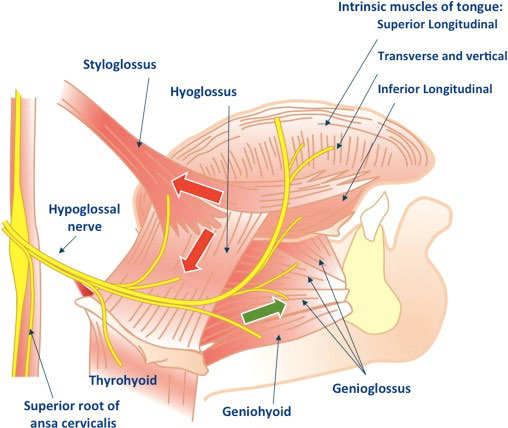

Muscle

Extrinsic muscles

Motor:CN XII

移動舌頭

- Genioglossus(makes bulk of the tongue)

- Hyoglossus

- Styloglossus

Motor:CN X (Pharyngeal plexus)

- Palatoglossus

Intrinsic muscles

Motor:CN XII

改變舌頭形狀

- Sup. longitudinal

- Inf. longitudinal

- Transverse

- Vertical